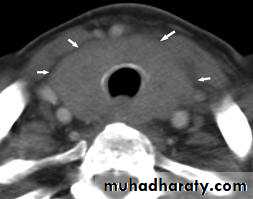

26CT scan of the neck

Nodule

Diffuse enlargementTuesday, November 04, 2014